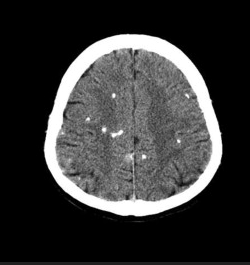

This is the finding on this CT.

What is subarachnoid hemorrhage?